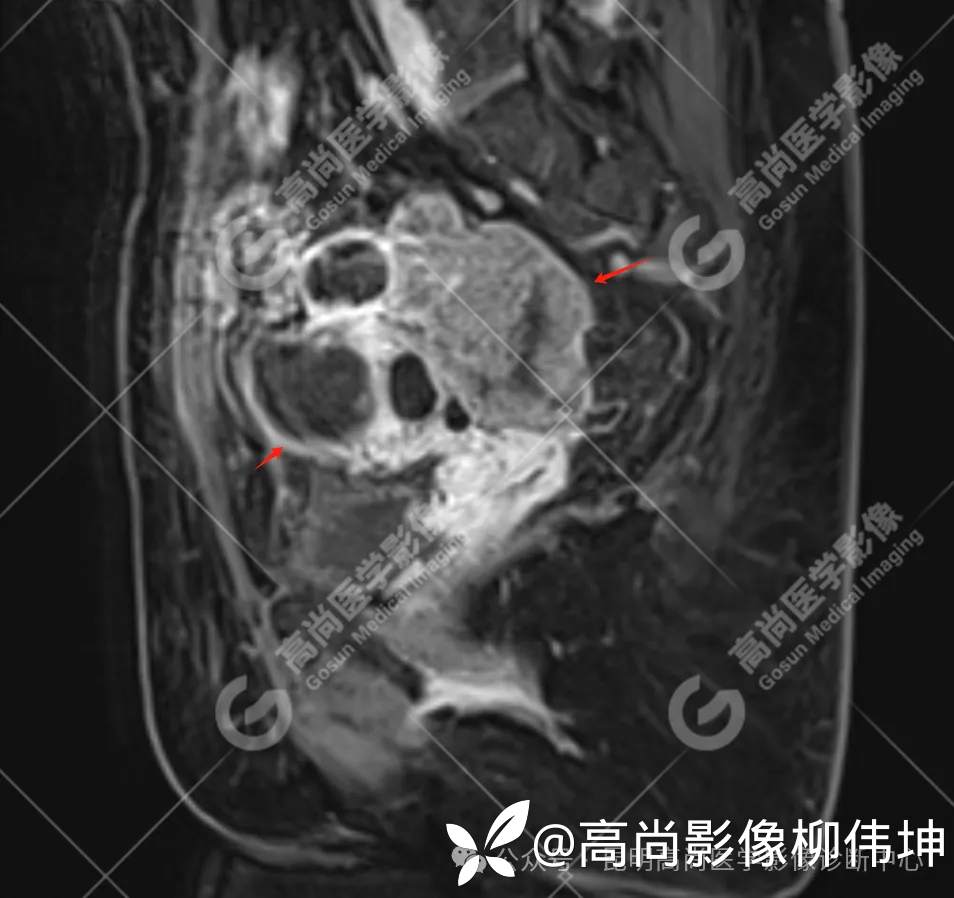

T2WI-sag

(2)MRI表现:通常双侧发生,体积巨大,呈外生性、囊实性、乳头状生长,其内见大量长T1长T2液性信号影及线性分隔,囊壁厚薄不均,可见壁结节及不同比例实性成分,呈T1等信号,T2略高信号。扩散受限,DWI呈高信号,ADC呈低信号。增强扫描实性成明显强化。另外,常可检出腹水、腹膜增厚、盆壁及盆腔脏器受累、淋巴结肿大等表现。